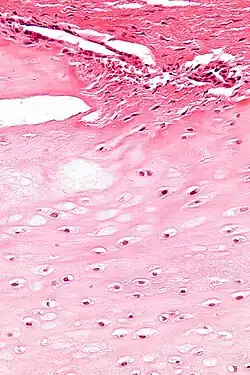

Micrograph of an enchondroma. H&E stain. |